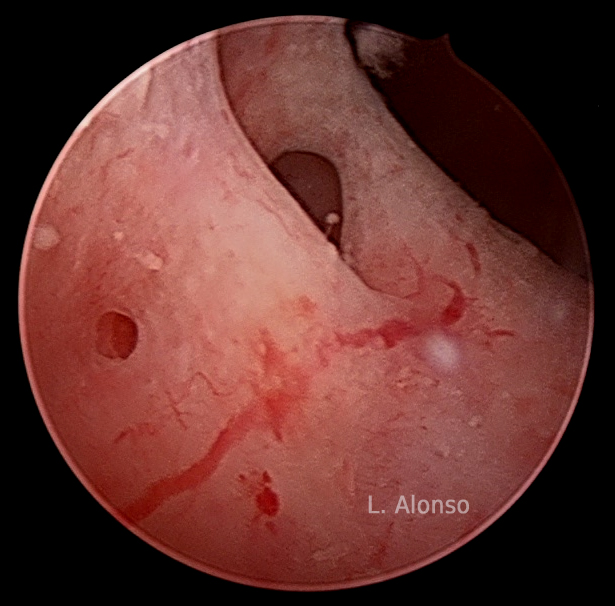

Luis Alonso Pacheco. Centro Gutenberg. Málaga. Spain INTRODUCTION Adenomyosis is defined as the presence of ectopic endometrial tissue inside the myometrium. This accumulation of endometrial glands and stroma in the myometrium causes hypertrophy of the surrounding myometrium. It was described for the first time by Rockitansky in 1860 when observing the existence of glands and…